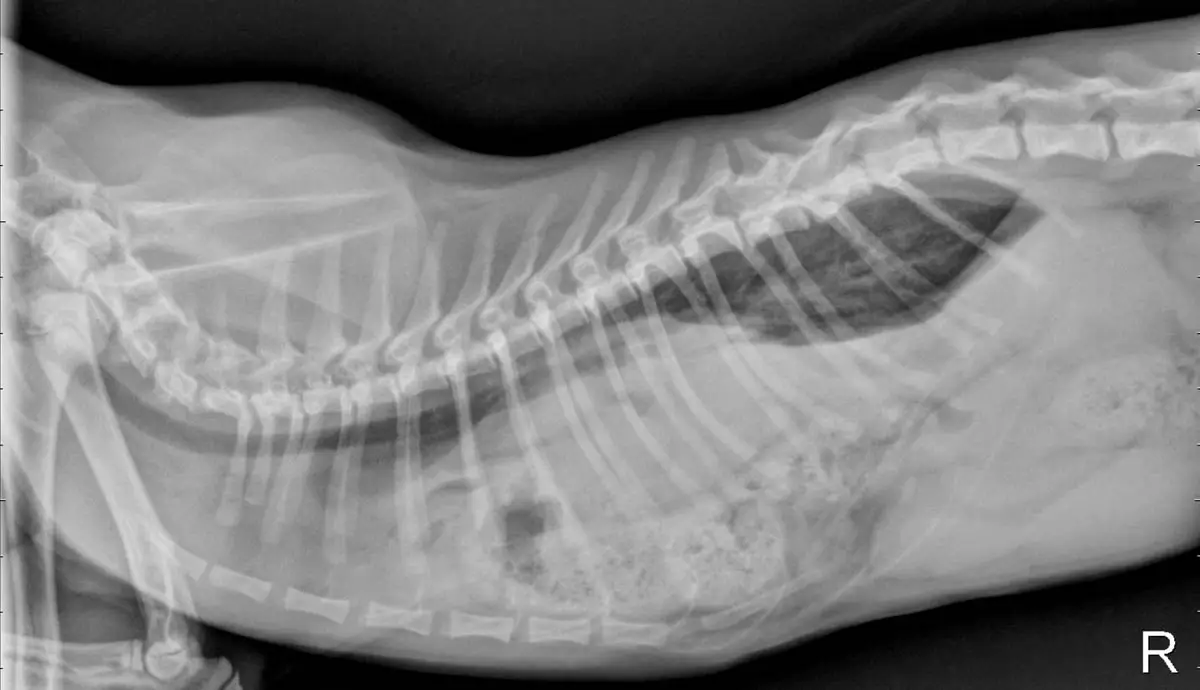

سوف تكشف الصور الشعاعية في البطن والصدر عن أعضاء في الصدر وفقدان خط الحجاب الحاجز.